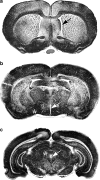

Endothelin-1 (ET-1) is an endothelium-derived peptide that also possesses potent mitogenic activity. There is also a suggestion the ET-1 is a neuropeptide, based mainly on its histological identification in both the central and peripheral nervous system in a number of species, including man. A neuropeptide role for ET-1 is supported by studies showing a variety of effects caused following its administration into different regions of the brain and by application to peripheral nerves. In addition there are studies proposing that ET-1 is implicated in a number of neural circuits where its transmitter affects range from a role in pain and temperature control to its action on the hypothalamo-neurosecretory system. While the effect of ET-1 on nerve tissue is beyond doubt, its action on nerve blood flow is often ignored. Here, we review data generated in a number of species and using a variety of experimental models. Studies range from those showing the distribution of ET-1 and its receptors in nerve tissue to those describing numerous neurally-mediated effects of ET-1.